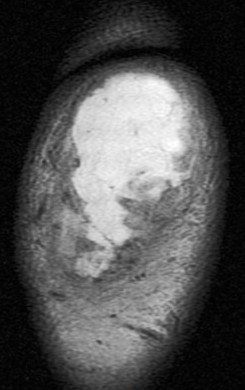

Figure 3 for case olecranon bursitis ( RID2082 )

Figure 3

Fluid and bursal lining thickening. Area edema. This was non septic. No osteomyelitis. Reference article.

olecranon bursitis ( RID2082 )